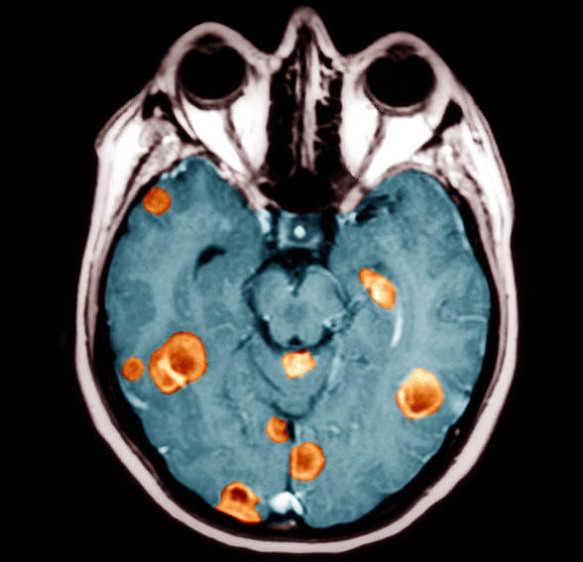

뇌종양을 진단하기 위해서는 신경학적 검사와 CT, MRI 등의 여러 검사를 시행하게 되고, 혈관의 분포와 주위의 혈관 관계를 보기 위하여 뇌혈관조영술을 진행하게 됩니다.

그리고 더욱 정밀한 검사가 필요할 때는 방사선동위원소검사와 뇌파검사 등을 진행할 수 있으며, 종양세포의 대사적 활성도를 영상으로 확인해 뇌종양의 악성도를 예측하는 양전자방출 단층촬영(PET) 등을 시행하기도 합니다.